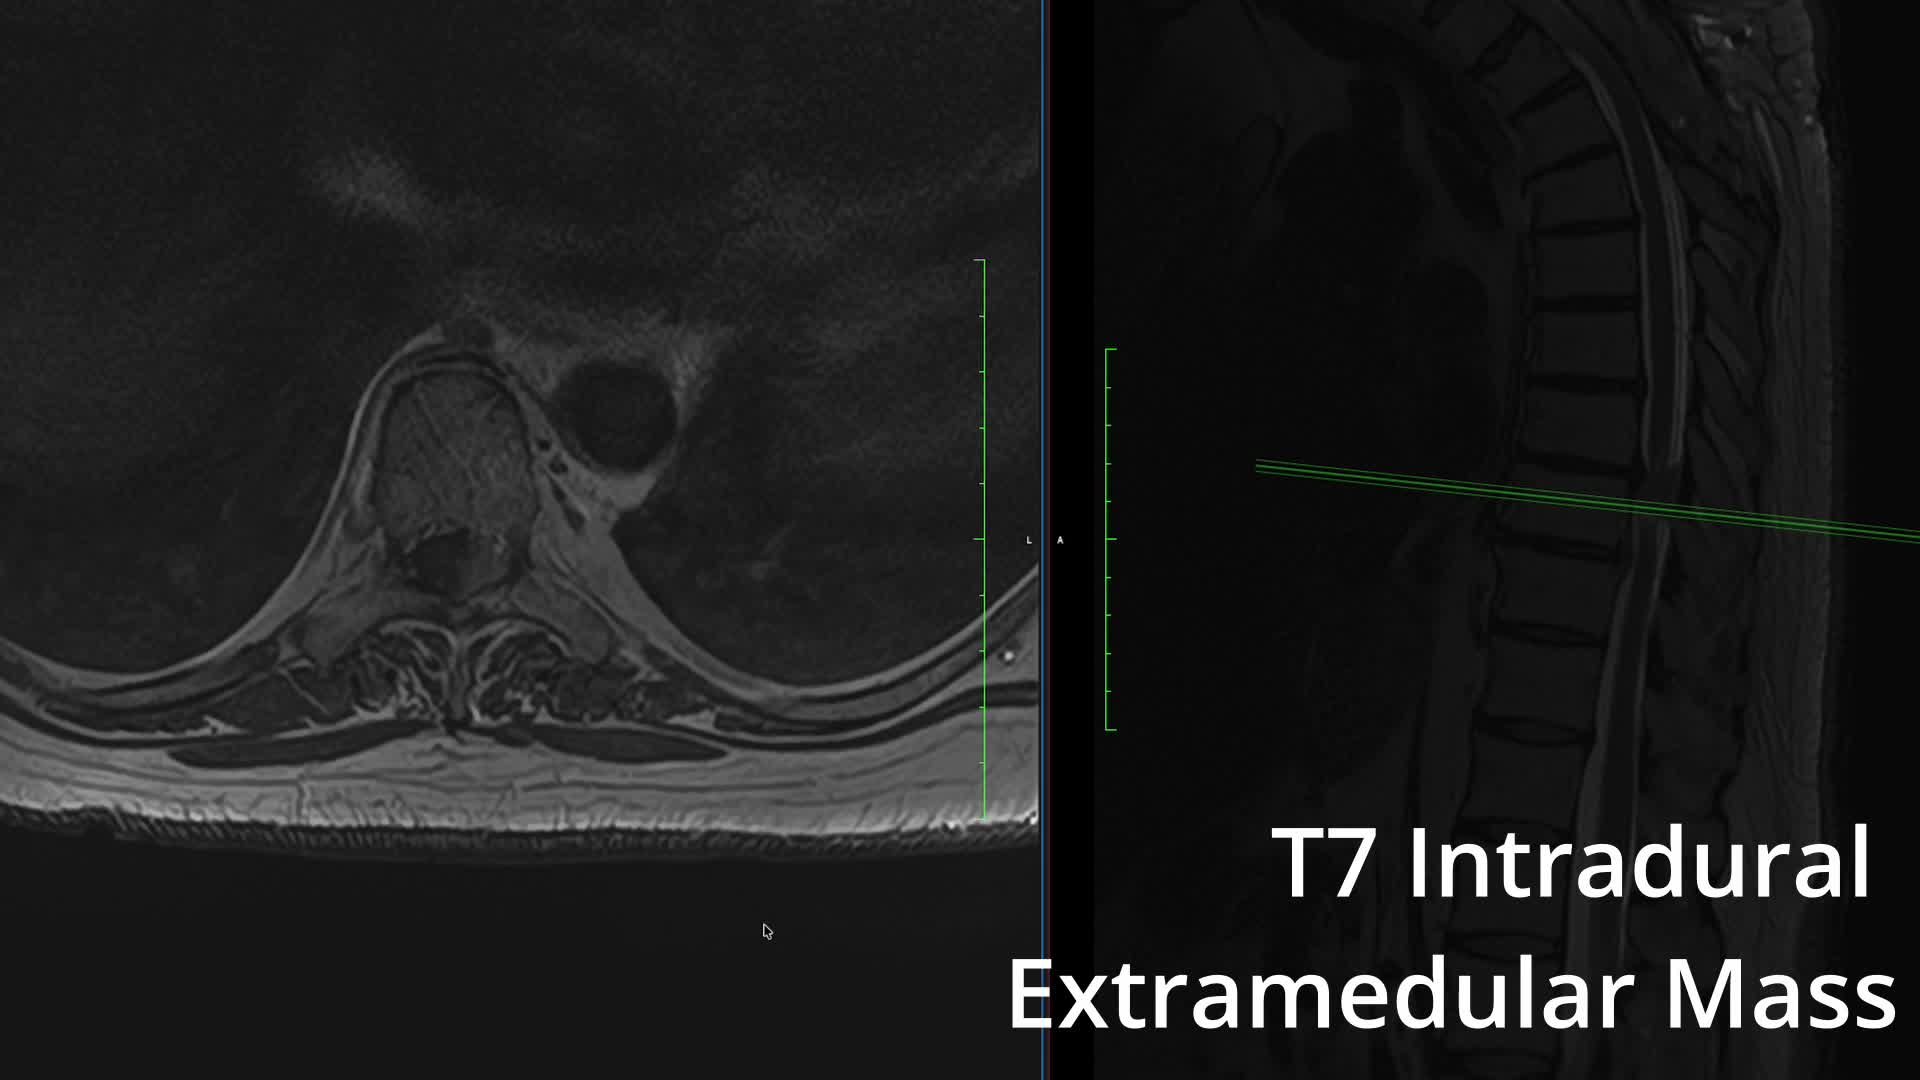

Videos Quirúrgicos Saltar a Vídeos Todo | Degenerativa | Tumores | Endoscopia | Tumores, • 6/1/26 Meningioma Dorsal 9/12/25 Anterior Cervical Discectomy and Fusion (ACDF) Degenerativa, • 3/6/25 eXtreme Lateral Interbody Fusion (XLIF) Degenerativa, • 3/6/25 Anterior Lumbar Interbody Fusion Degenerativa, • 3/6/25 Extraforaminal Hernia Microdiscectomy 2/6/25 Spinal Schwannoma Tumores, • 1/6/25 Spinal Astrocytoma Tumores, • 1/6/25 Spinal Neurofibroma